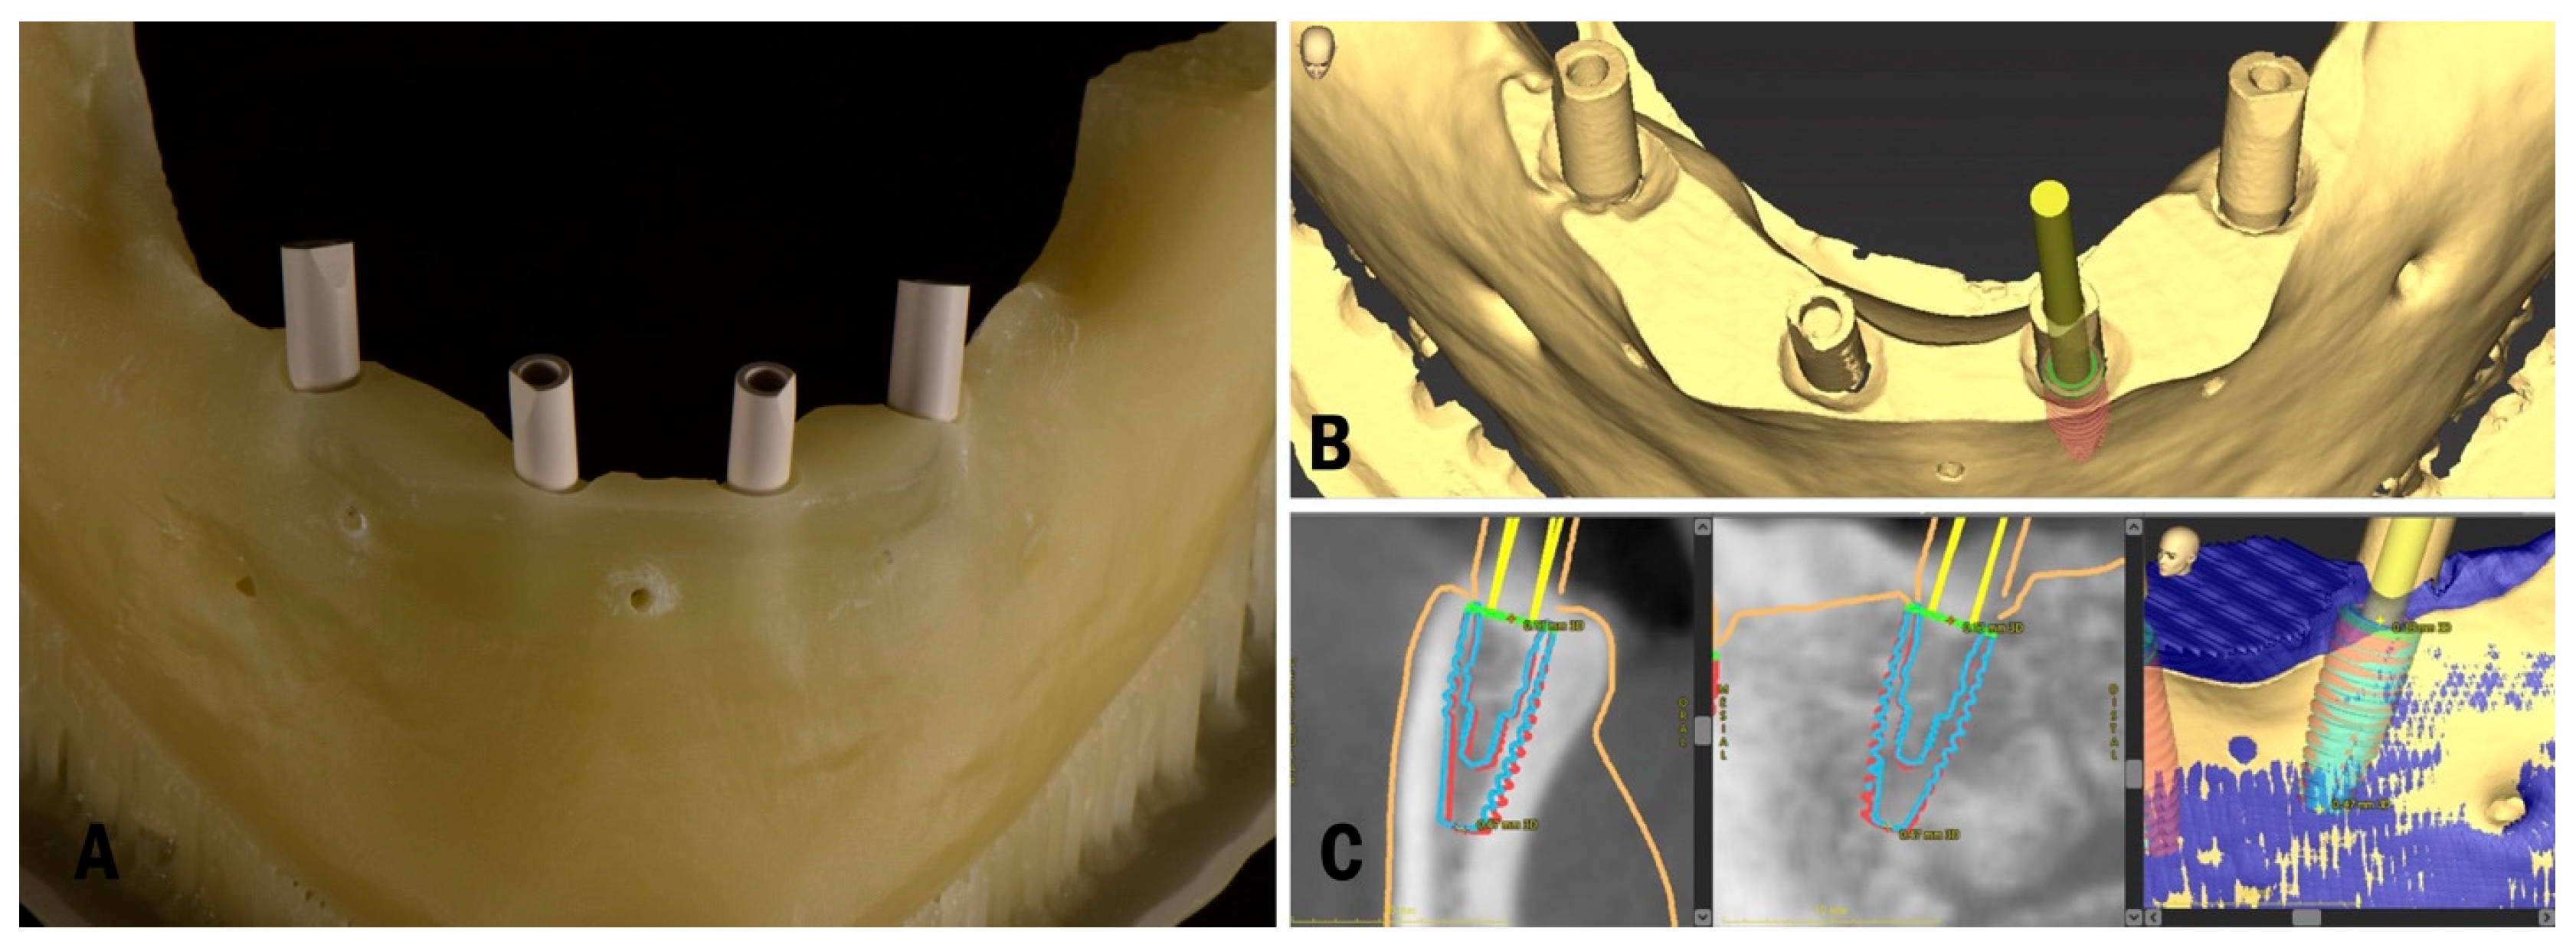

2. Materials and Methods

2.1. Planning and Surgery

3.2. In Vitro Treatment Evaluation